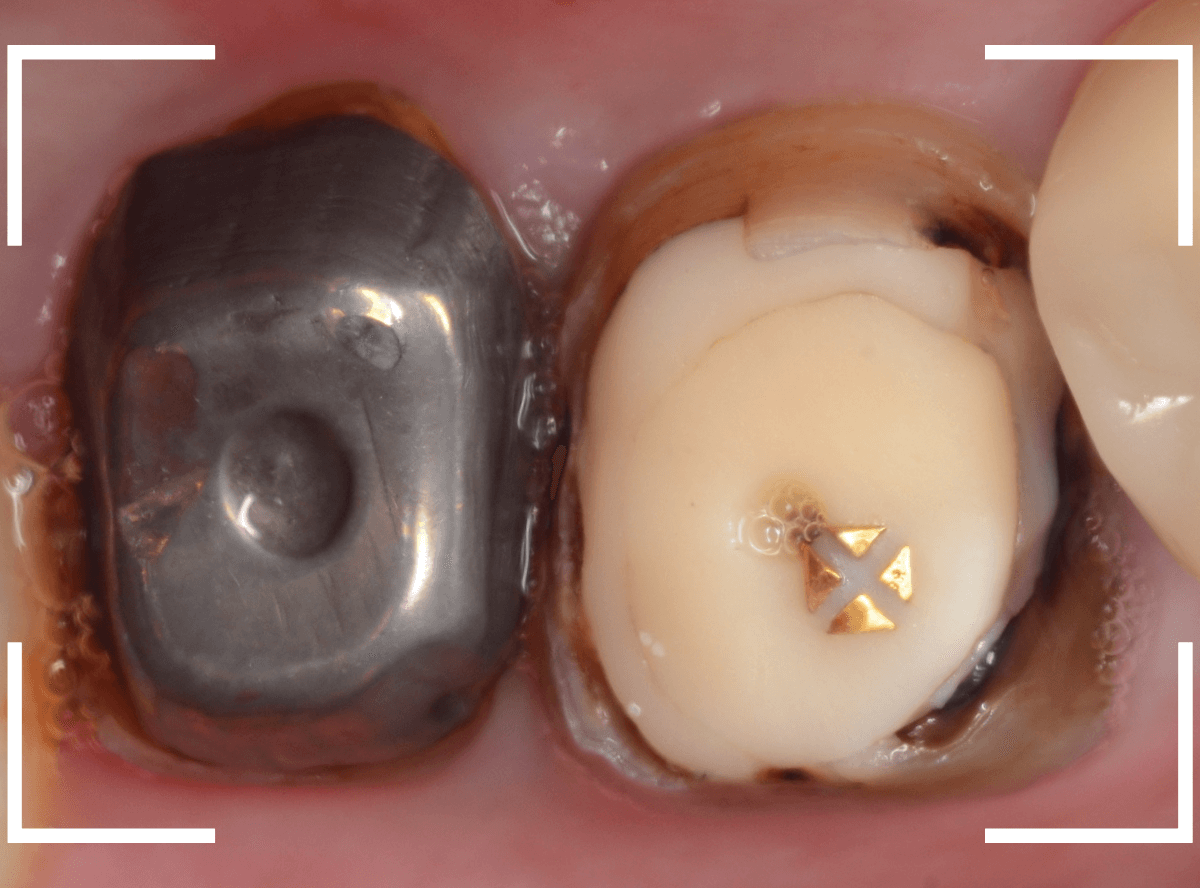

Case.1

こちらは比較的簡単な歯の土台の再治療のケースです。

下の奥歯の虫歯の治療後に、金属の土台(メタル・コア)をsetして、長期間放置してしまいました。

見た目的にはあまり問題なさそうにみえましたが、奥歯との間の歯肉が若干炎症気味でぶよぶよしてるのが気になりました。

レントゲン写真で確認すると、歯の奥側が虫歯になり始めています。

虫歯のすき間に物がつまりやすくなり、歯肉の状態がイマイチだったのかもしれません。

この虫歯を除去しないままさし歯をお作りしても、よい治療にはなりません。

短期間で外れて再治療になる可能性も高いですので、まずは虫歯の再治療をします。

メタル・コアを除去して、明視野で虫歯を確認します。